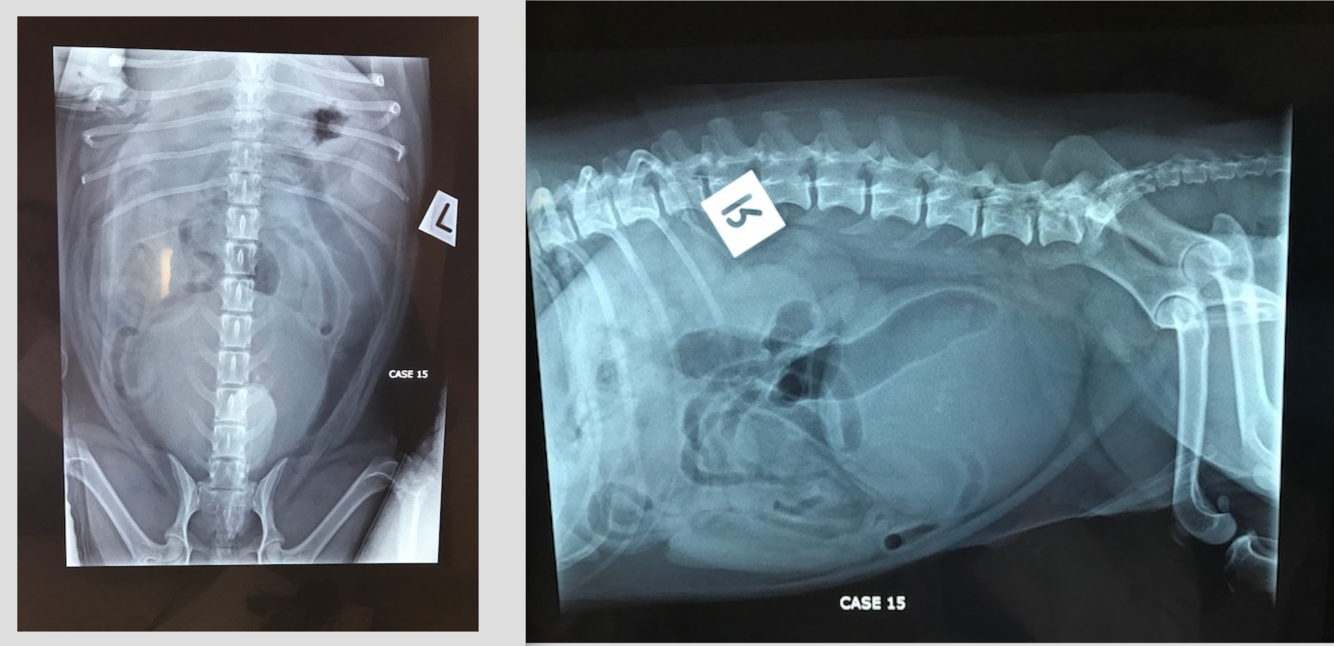

1 yo MN Burmese

5 week history of weight loss and reduced appetite

CE: Abdo palpation: pain on palpation with thickened intestinal loops/poss descending colon palpable. Estimate poss < 5% dehydrated.

DDX decreased intraserosal detail? Most likely?

Rule for assessing gastric distension?

Oval, comma shaped and C shapred SI throughout the mid abdomen? What is the rule for SI overdistension in the cat?

The distended loop of intestine containing fragmented gas opacities within the cranioventral abdomen on the lateral projection within the right cranial abdomen on the VD projection– do think this is SI or LI?

Stomach– no greater than 3 ICS– fundus typically 2 x wide as pylorus